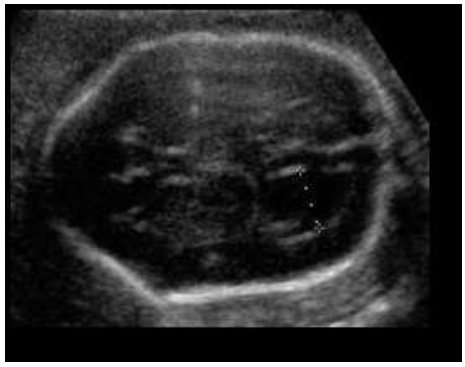

III - As estruturas assinaladas na imagem abaixo, correspondem ao diencéfalo (1) e ao tronco cerebral/ponte e bulbo (2).

IV - A imagem deve estar ampliada de maneira que apenas a cabeça e a parte superior do tórax sejam vistas.